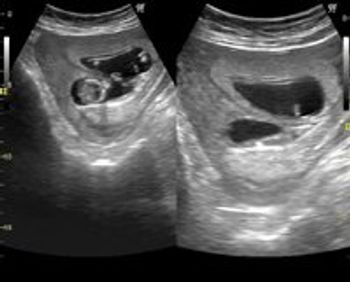

These are ultrasound images of an early pregnancy.

There are multiple anomalies in these ultrasound images of a second trimester pregnancy.